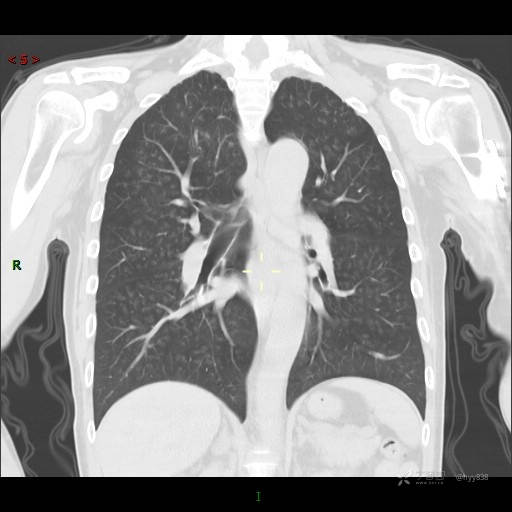

性别:男

年龄:55岁

简要病史:渐进性呼吸困难。

实验室检查:血象正常。

临床诊断:呼吸困难待查

胸部CT平扫